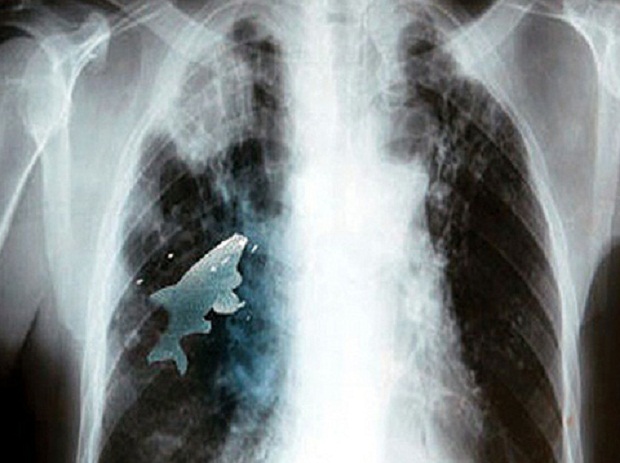

У ребенка затруднилось дыхание, началось удушье, и он был срочно доставлен в больницу. Рентген показал, что в его легких находится еще живая рыба.

Анилу сделали срочную операцию по извлечению рыбы из легкого. Оперировавшие его хирурги сказали, что никогда ранее в своей практике не сталкивались с такой ситуацией.